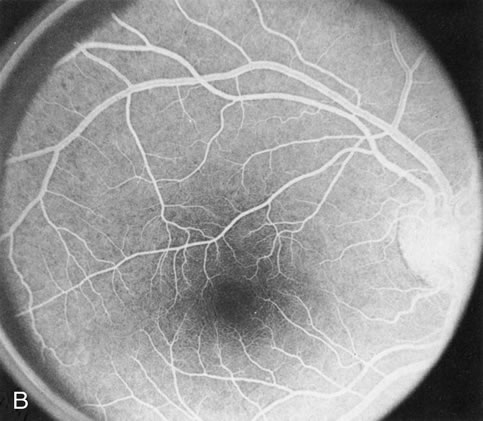

Fig. 1. Retinitis pigmentosa. A. A typical area of bone spicule pigmentation. B. Diffuse dye leakage is apparent throughout the posterior pole. C. The early angiogram shows dilated and irregular retinal radial peripapillary capillaries and perifoveal retinal capillaries. D. Leakage from these vessels are evident in the late angiogram.

Dye leakage in RP may occur from the retinal vessels or at the level of the retinal pigment epithelium (Fig. 1B).2–4 The leakage may be seen in the macula and posterior pole, along the vascular arcades in the distribution of the radial peripapillary capillaries, and in the periphery (where an exudative vasculopathy resembling Coats' disease is suggested).

Of more clinical importance is the role of FA in the diagnosis and treatment of cystoid macular edema (CME) (Fig. 1C and D). Stereoscopic FA indicates that the leakage, which may be diffuse or have the typical petaloid stellate appearance of CME, can come from the perifoveal retinal capillaries, from the choroid through the RPE, or from a combination of both sources.4 With the recent suggestion that CME in RP may be successfully treated with acetazolamide,5, 6 FA is thus important to document the diagnosis of CME, establish the origin(s) of leakage, and follow patients during and after therapy.